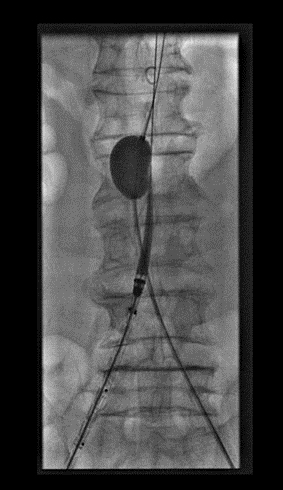

患者的病情在进行性加重,术前血压已低至76/40mmHg,立即紧急手术!平素以胸腹主大动脉疾病诊治见长的栾景源副主任,凭借丰富的临床经验,迅速以球囊临时阻断肾下腹主动脉,达到了明显减缓出血、维持血压的效果。(如图3)

图3